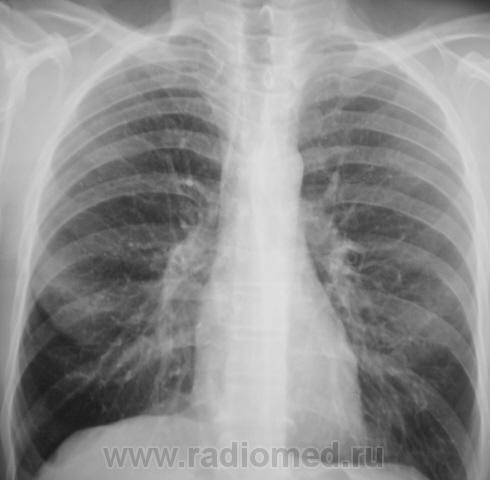

Распад был изначально, но, к счастью больного, все закончилось практическим выздоровлением.

Долго что-то пневмонию лечили. А распад очень сомнительный. Больше на игру теней похож.

Да, лечение весьма затянулось.